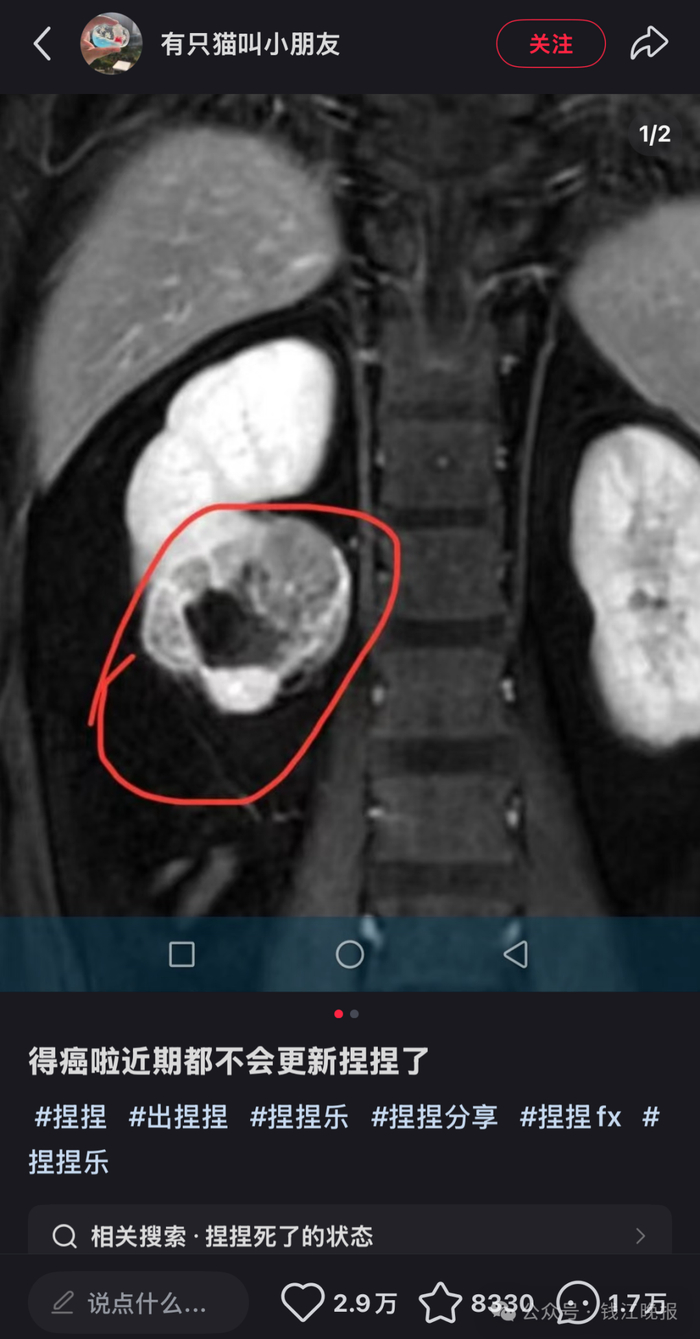

然而,近日一位解压“捏捏”玩具博主

自曝患癌的消息

令公众对于“捏捏”玩具

潜在健康风险的担忧进一步加剧

该博主在社交媒体上发文透露自己罹患癌症,并宣布将暂时停止更新与“捏捏”玩具相关的视频内容。

此举迅速引发了网友的广泛关注和讨论。虽然该博主在文案中并未提及具体的患癌原因,但在评论区,有不少网友怀疑其患癌原因与长时间接触“捏捏”有关。